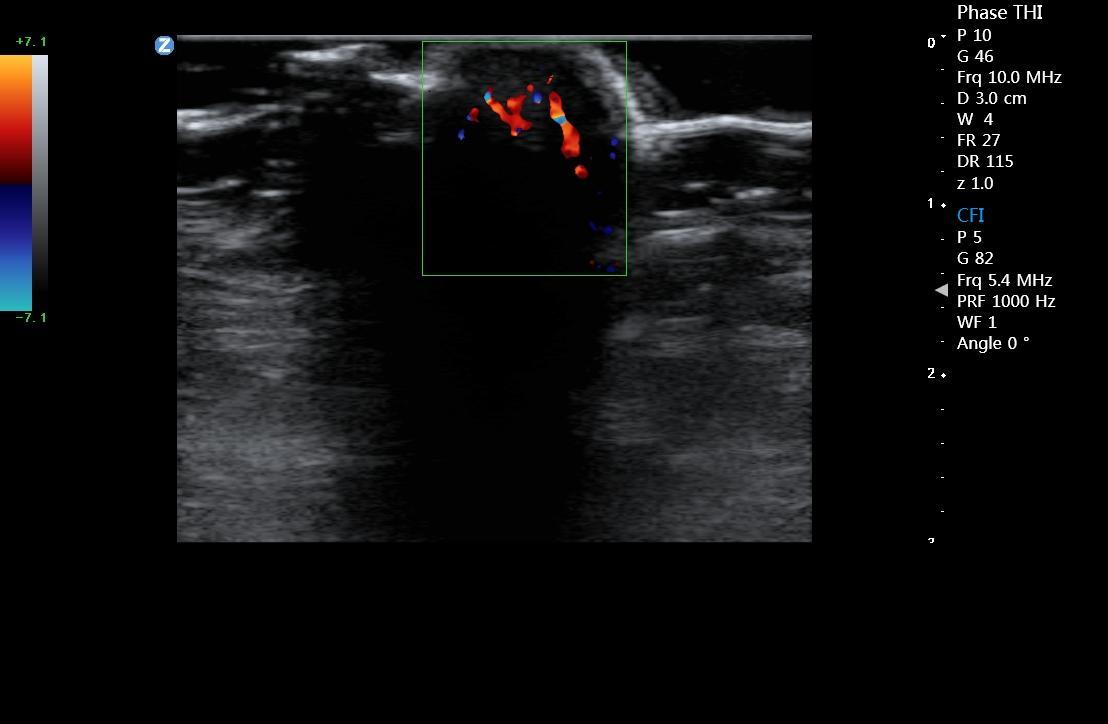

微血流成像 zMicroflow

显著提升肾脏、心肌内膜、淋巴结等组织内部微血管彩色血流信号的显示能力,真实反映血流变化情况